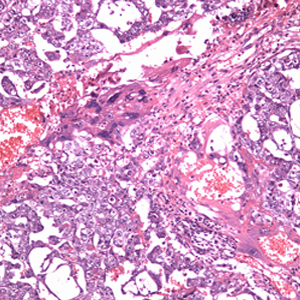

Bildeeksempler:

Embryonalt karsinom

Embryonalt karsinom er den nest hyppigste type av germinalcellesvulster i testiklene. Svulstcellene er relativt store, med kjerner som avviker grovt fra det normale. Tumoren kan vokse solid, med kjertler eller papillære strukturer.

Teratomene innholder forskjellige vevstyper og imiterer umodent fostervev eller mer modent vev. Umodne komponenter er ofte neuroektodermalt eller mesenkymalt vev, mens mer modne komponenter ofte er cystiske med forskjellige typer av epitel eller består av glatt muskulatur, bindevev eller brusk. Fordi teratomene ofte inneholder en blanding, er man gått bort fra den tidligere inndeling i modne eller umodne teratomer. De ulike vevselementene i teratomer kan av og til utvikle en sekundær ondartethet av såkalt somatisk type (tidligere kalt ”malign transformasjon”). Eksempel er utvikling av platepitelkarsinom i et område med hud-differensiering i teratomdelen av germinalcellesvulsten.